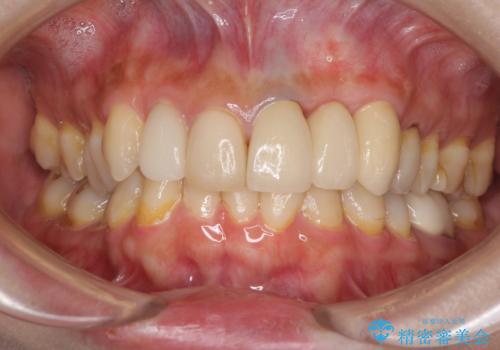

歯肉移植を用いた前歯のオールセラミックブリッジ

- 前歯が折れてしまい、ブリッジによる補綴治療を希望して来院された患者様です。

折れている前歯は抜歯をし、痩せてしまう歯肉は移植術により増大させることで審美面を回復した後、オールセラミックブリッジにて補綴することとしました。

インプラントかブリッジか悩むところでしたが、既に治療されている前歯のクラウン周りの変色が気になっていたため、ブリッジにより色調を合わせたオールセラミックを装着することを選択しました。

歯肉ラインや歯の形態、色調を整えることができ、患者様には大変満足していただきました。